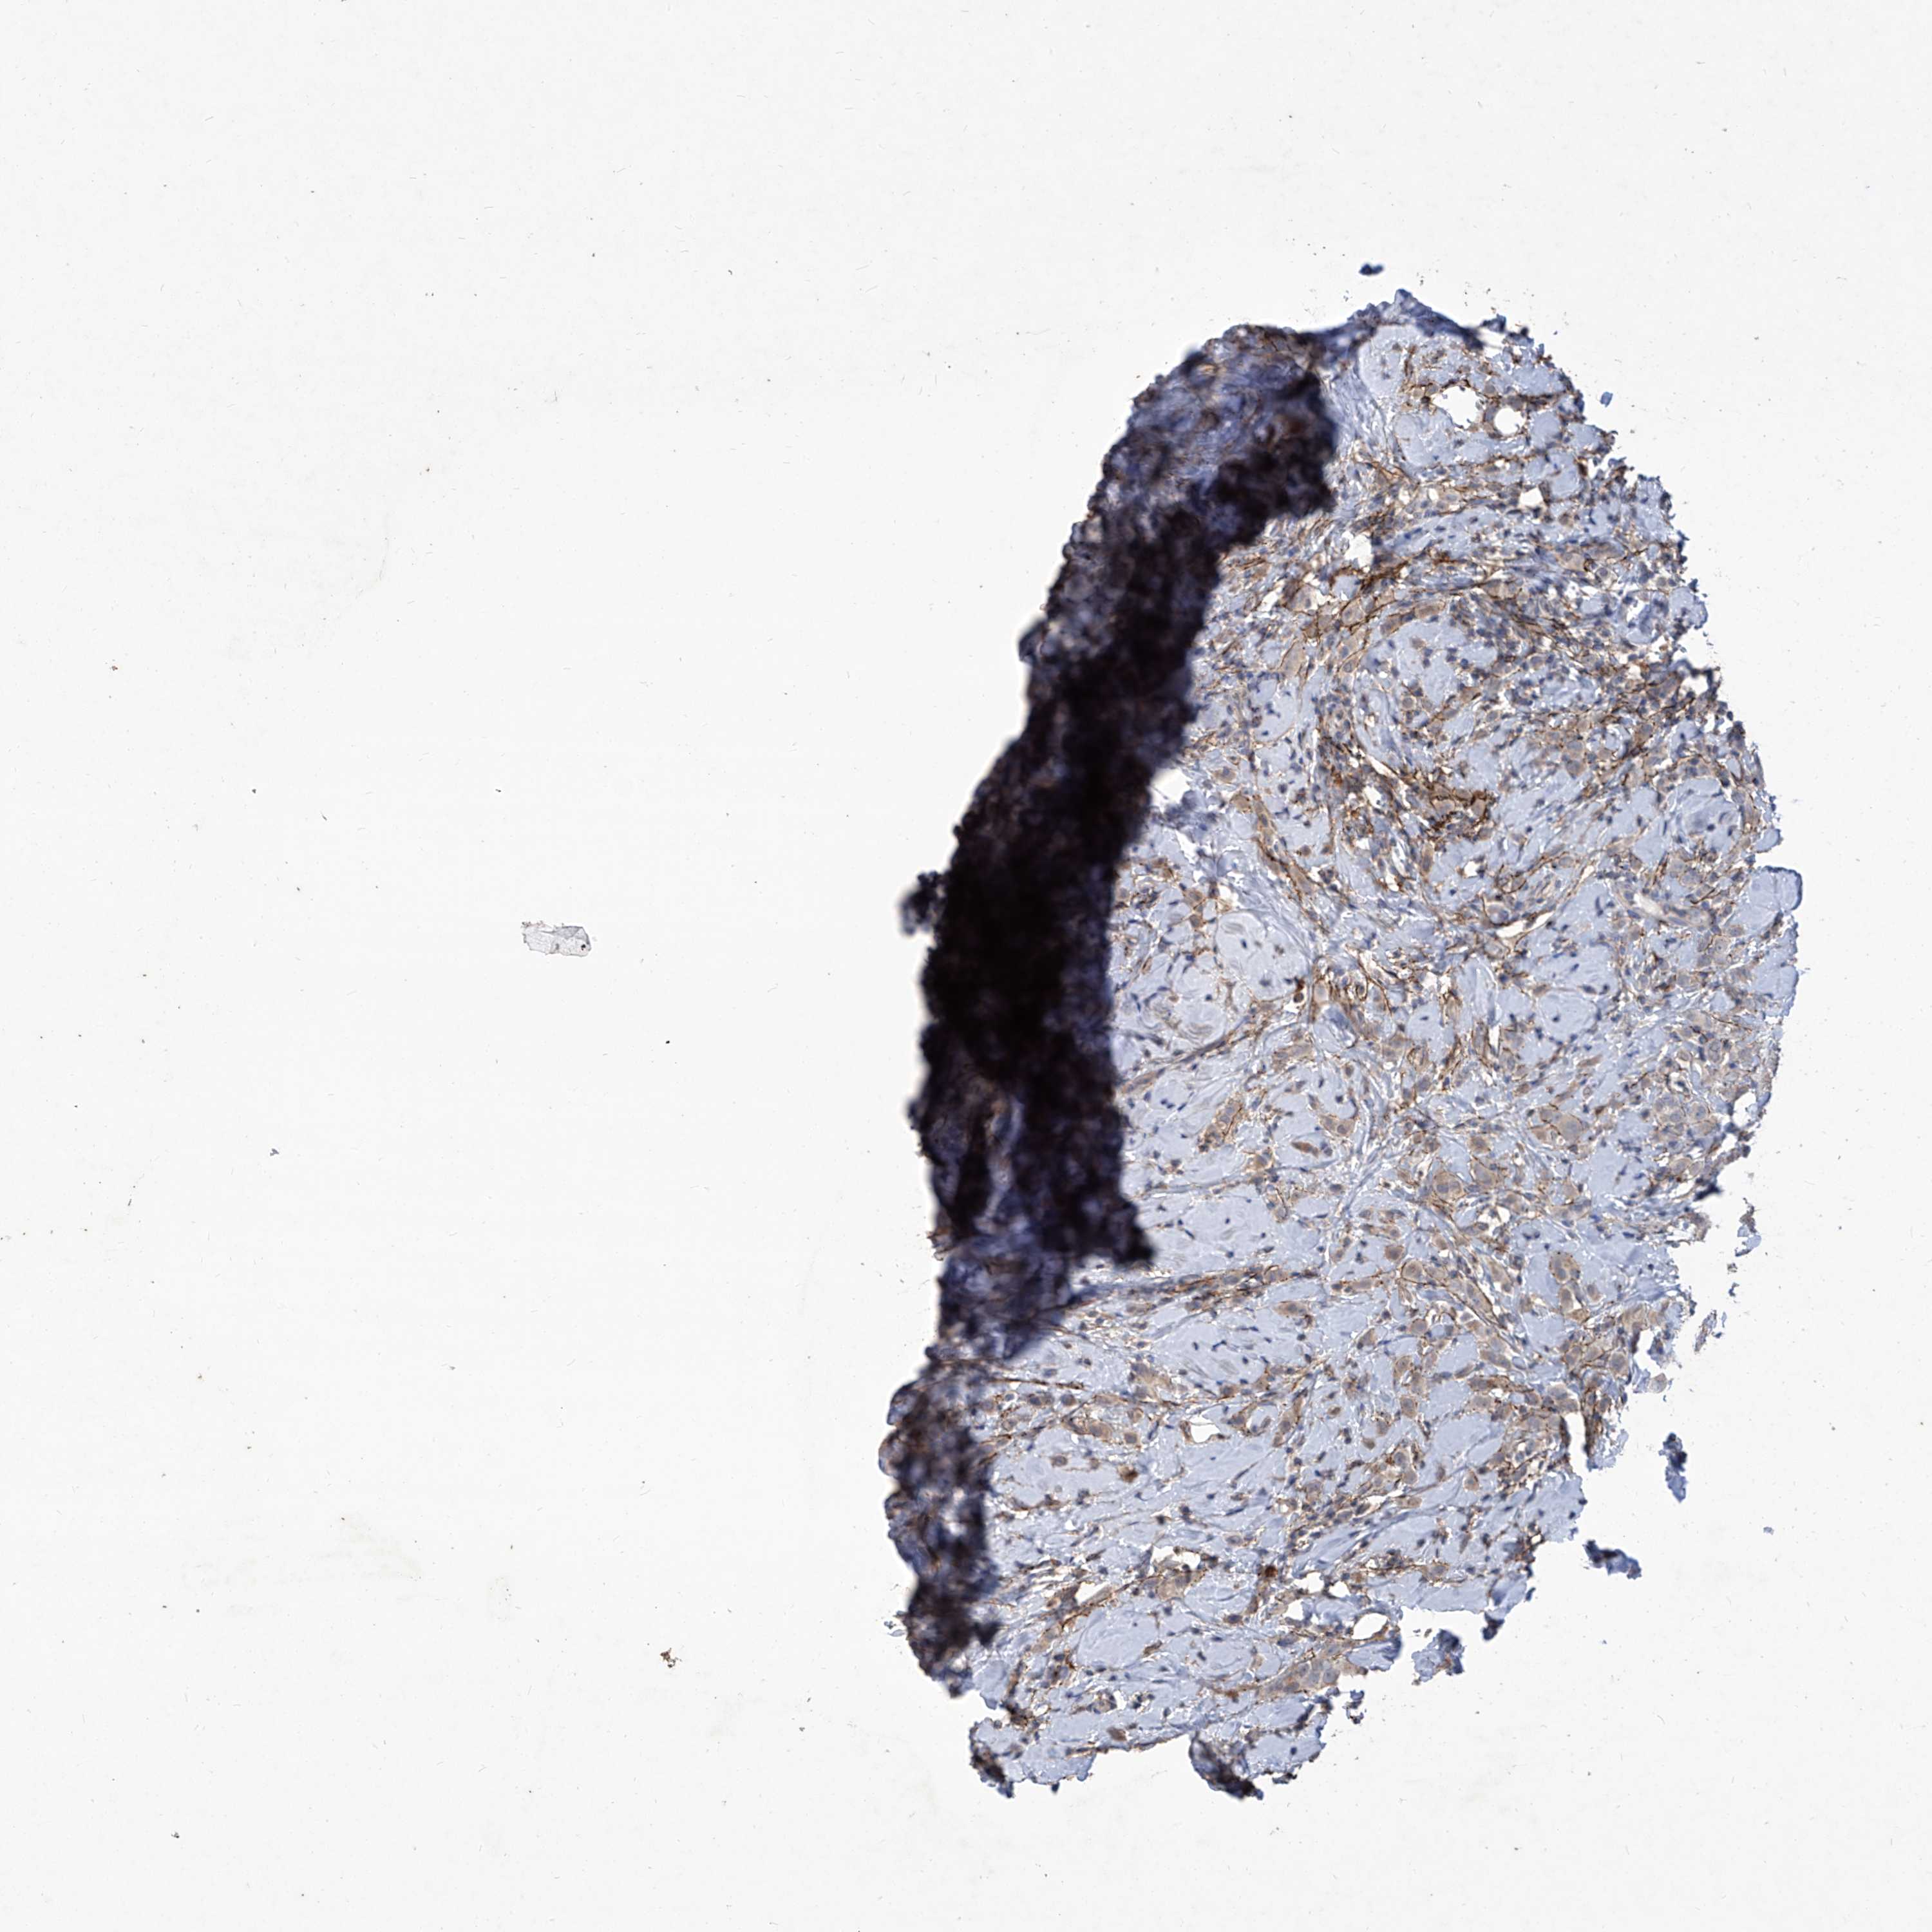

CANCER BREAST CANCER Show tissue menu

BRCA TCGA BRCA VALIDATION PROTEIN EXPRESSION

Breast cancer

Human cancer

Breast invasive carcinoma